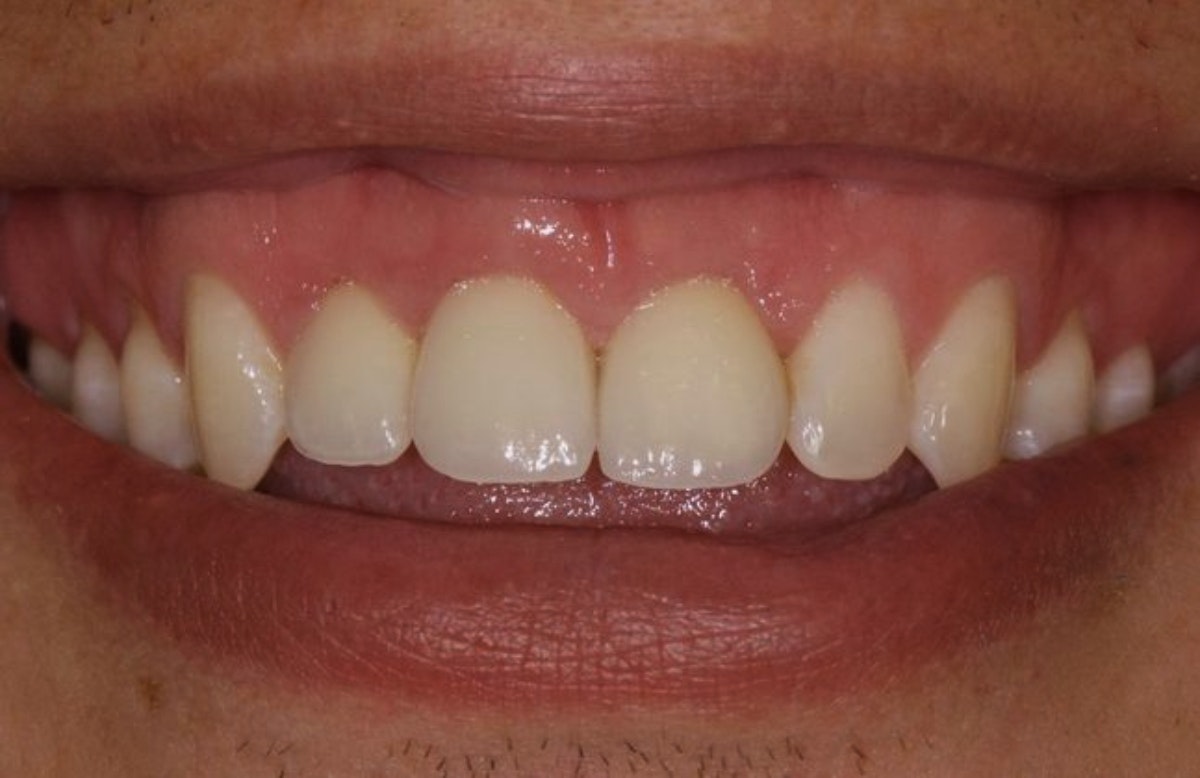

Patient with three implant-supported restorations

After

This patient lost multiple teeth in a scooter accident. We replaced their lost teeth with three implant-supported restorations. The result looks natural, didn't require crowning any teeth to support a traditional bridge, and will prevent the jaw atrophy that occurs in the absence of tooth roots.